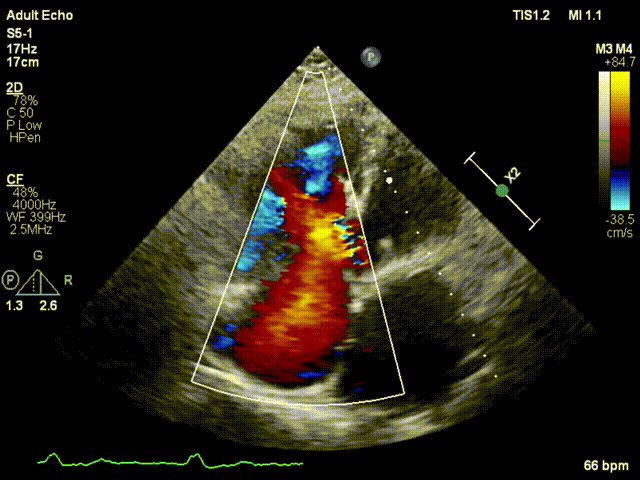

本次接受治療的患者是一名74歲的女性,14年前因風(fēng)濕性心臟病行二尖瓣生物瓣植入術(shù),合并房顫。近3年來反復(fù)因腹脹、納差、下肢水腫入院,藥物治療欠佳。心臟超聲顯示三尖瓣極重度反流(有效反流口面積:0.76cm²,反流容積:79ml),繼發(fā)性右房室增大及上、下腔靜脈增寬(右房上下徑*左右徑:52*41mm,右室左右徑:46mm,下腔靜脈:29mm),右室收縮功能正常,肺動(dòng)脈收縮壓 43mmHg,左心室射血分?jǐn)?shù)73% ?;颊呒韧_胸手術(shù)史,術(shù)前評(píng)估STS 評(píng)分為7.02分,CRS 9分,無法接受體外循環(huán)下三尖瓣外科手術(shù)。面對(duì)這一傳統(tǒng)治療無法解決的困境,葛均波院士及其團(tuán)隊(duì)周達(dá)新教授、潘文志教授、張?jiān)床┦俊㈥惿┦考靶某业呐舜湔浣淌?、李偉教授?jīng)過討論決定,采用創(chuàng)新的Lux-Valve Plus系統(tǒng)為患者進(jìn)行經(jīng)血管三尖瓣置換。

手術(shù)在患者全麻狀態(tài)下進(jìn)行,采用經(jīng)右側(cè)頸靜脈作為入路,將裝載有人工瓣膜的輸送器緩慢推送至右心房;并在經(jīng)食道超聲和DSA的引導(dǎo)下小心調(diào)整輸送器角度,將輸送器送入右心室;逐步釋放瓣膜錨定裝置和盤片,調(diào)整瓣膜位置后,錨定瓣膜完成植入。術(shù)后右房壓明顯下降,從術(shù)前的25/10(16) mmHg降至術(shù)后即刻的12/7(10) mmHg,術(shù)后超聲提示人工三尖瓣同軸性良好,固定牢固,無反流及瓣周漏,手術(shù)室即刻拔除氣管插管。